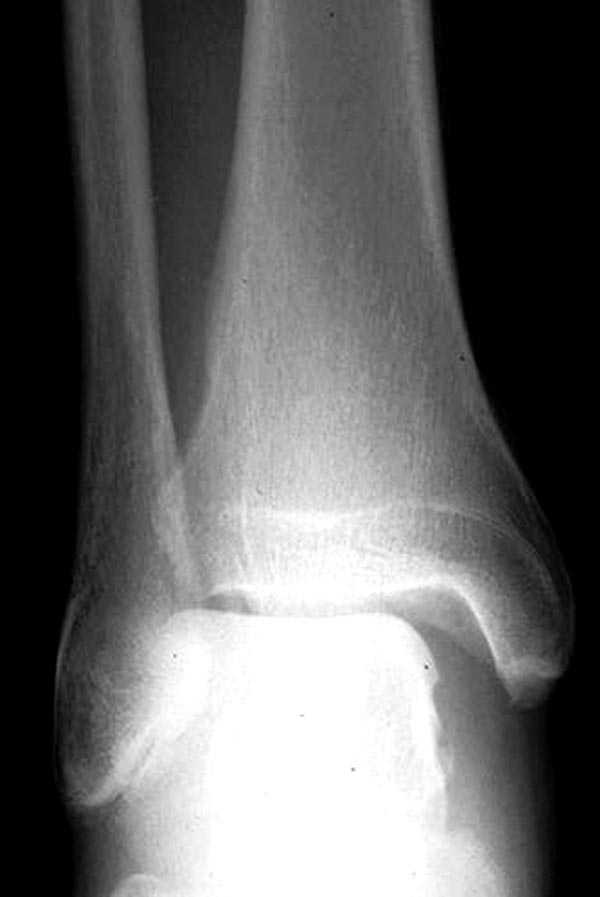

Здесь как раз тот случай, когда рентгеновский снимок скрывает главную проблему. "Ходит, прихрамывая на правую ногу, отмечает боли в правом голеностопном суставе" По описанию клиника типичная для повреждения голонестопного сустава - синдесмоза.

Для уточнения диагноза надо сделать все стандартные снимки голеностопа, (несмотря на необходимость при любых повреждениях голеностопа, почему-то очень трудно воспроизводится коллегами из СНГ?)

На прямой проекции можно увидеть расширенную медиальную щель, и на мортизе укорочение малоберцовой.

Без оперативного лечения Межкостная мембрана будет источником боли у спортсменов.